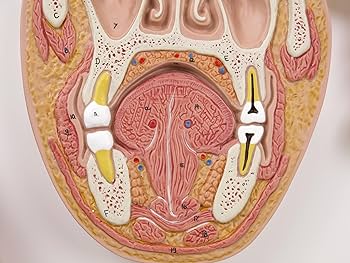

Amazon.co.jp: 脳や鼻腔・口腔などを矢状面と冠状面で観察できる断面模型 - 頭部断面モデル,正中矢状断,前額断 - 3BScientific : 産業・研究開発用品。

大脳 冠状断面<< 神経系 << バイオメディカル CG ライブラリー << 株式会社メタ・コーポレーション・ジャパン。

大脑冠状面和矢状面结构分解图PNG图片素材下载_图片编号2533656-PNG素材网。

脳 MRI 3D : 正常解剖学e-Anatomy。

经下丘冠状面层面 枕颞沟呈“11”型,白色实线为枕颞沟,红色实线为侧副沟。